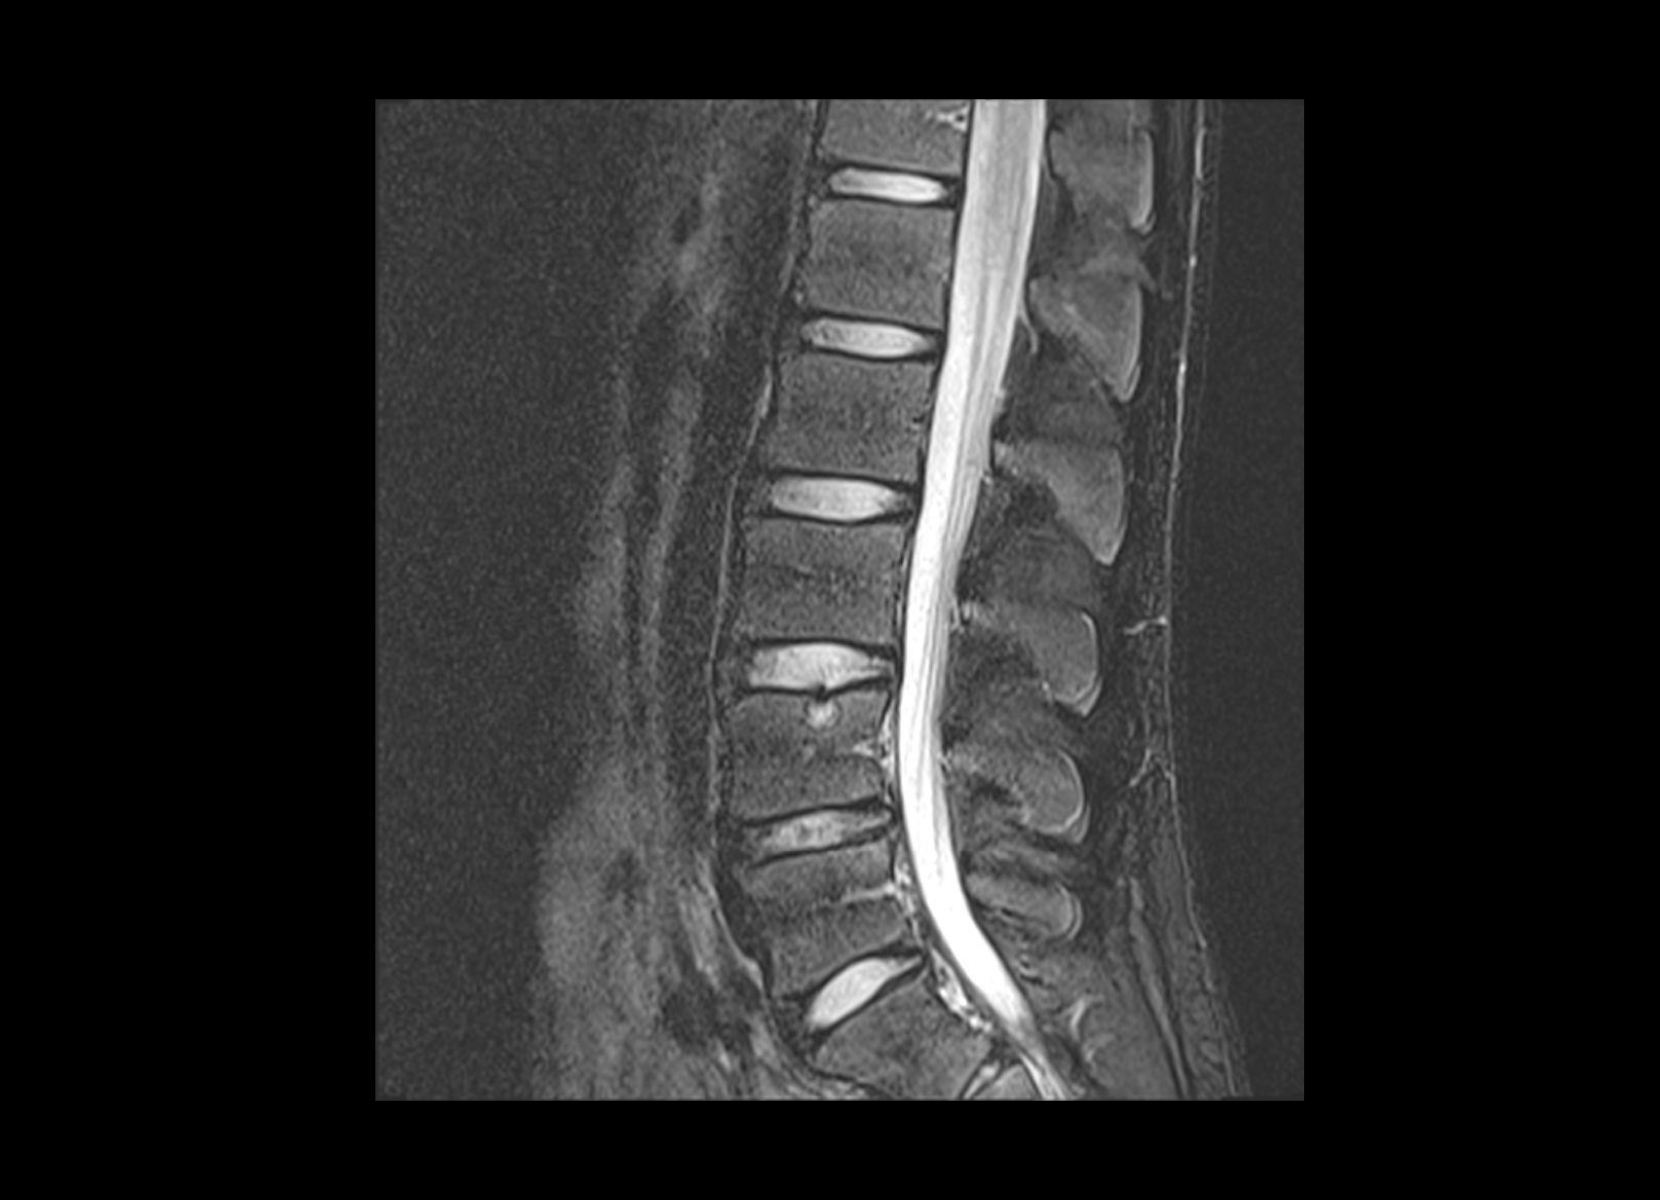

Conventional

STIR

SubtleSYNTH™

(Synthesized STIR)™

Trauma

GE 1.5T

C-spine